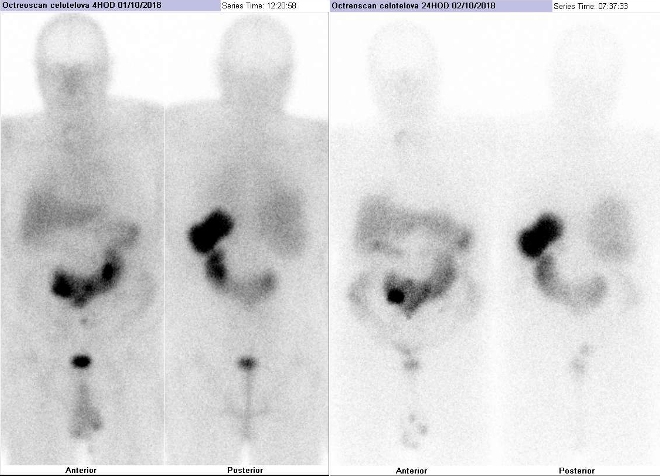

Scintigrafie Octreoscanem

Pomocí dvoudetektorové hybridní tomografické kamery Symbia T2 (SPECT/CT) firmy Siemens opatřené kolimátory pro střední energie jsme provedli celotělovou scintigrafii a také cílenou tomografickou scintigrafii (SPECT) a CT a fúzi obrazů SPECT/CT břicha s částí pánve, krku a hrudníku za 4 hod. a 24 hod.

(obr. 1-8) po i.v. podání 220 MBq analogu somatostatinu značeného

111In (přípravek OctreoScan firmy Mallinckrodt

Medical).

/ Obr. č. 1: Celotělová scintigrafie v přední a zadní projekci za 4 (vlevo) a 24 hod. (vpravo) po aplikaci radiofarmaka.

Je patrné ložisko se zvýšenou hustotou somatostatinových receptorů v mezenteriu pravého mezogastria. Dále jako vedlejší nález je patrná podkovovitá ledvina a mírně zvýšená depozice radiofarmaka v nodozní strumě s uzlem v pravém laloku.

U 73letého nemocného jsme pomocí vyšetření Octreoscanem prokázali neuroendokrinní tumor v mezenteriu pravého mezogastria.